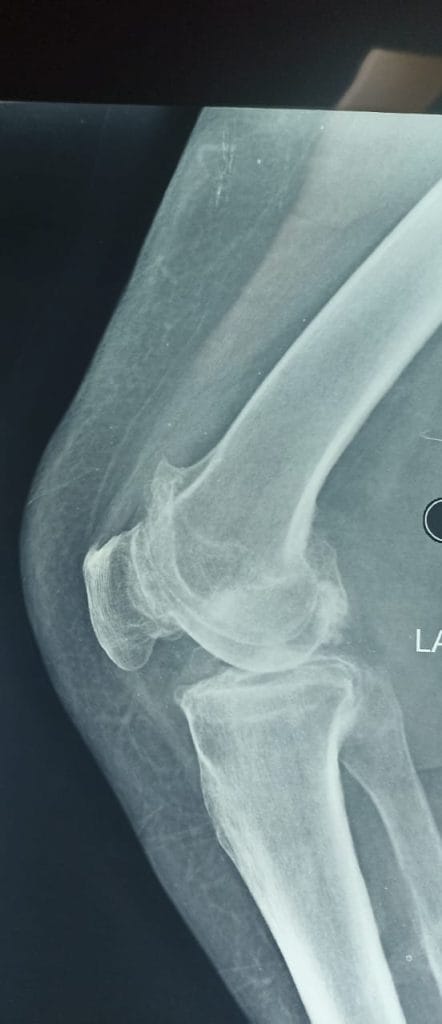

بتأريخ 2022/10/31 راجعت المريضة استشارية العظام والكسور في مستشفى ابن سينا التدريبي وكانت تعاني من ألم شديد في مفصل الركبه اليسرى ، وبعد اجراء الفحوصات السريرية والمختبرية والشعاعية تبين انها تعاني من سوفان شديد و تحدد في مفصل الركبه اليسرى .